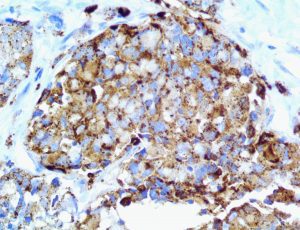

It is the ICU physician who is most likely to witness one of the deadliest manifestations of the abnormal immunological response, the cytokine storm syndrome (CSS). This response is also referred to by some as the cytokine release syndrome (CRS). CSS is characterized by continuous activation and expansion of macrophage and lymphocyte populations, which secrete large amounts of cytokines, causing the cytokine storm. This massive cytokine release is akin to hemophagocytic lymphohistiocytosis (HLH) disease, a syndrome characterized by initial unchecked and persistent activation of cytotoxic T lymphocytes and NK cells.

Clinical and laboratory manifestations of HLH include fever, enlarged liver and/or spleen, neurologic dysfunction, coagulopathy, liver dysfunction, cytopenias (i.e., low levels of erythrocytes, leukocytes, and/or platelets), hypertriglyceridemia, hyperferritinemia, hemophagocytosis, and eventually diminished NK cell activity as the immune system becomes progressively paralyzed. HLH can be familial (primary HLH) or secondary to another disease process (sHLH), such as rheumatic disease, in which it is referred to as macrophage activation syndrome (MAS, characterized by elevated ferritin).